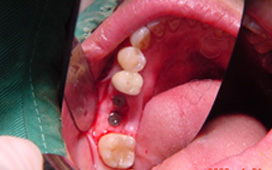

缺牙導致牙齒移位 - 臨床實例一

缺牙導致牙齒移位 - 臨床實例二